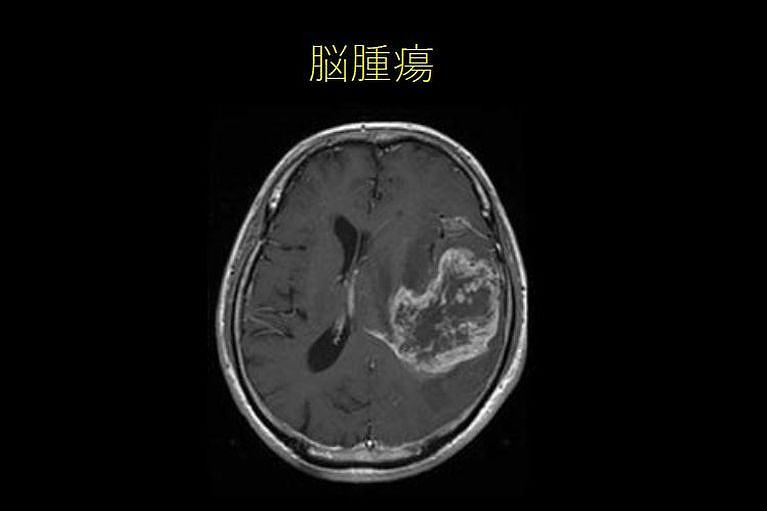

脳腫瘍

• 慢性進行性、早朝時頭痛

• 吐き気のない突然の嘔吐

• けいれん発作、神経局所症状(言語障害、視野障害、運動障害など)